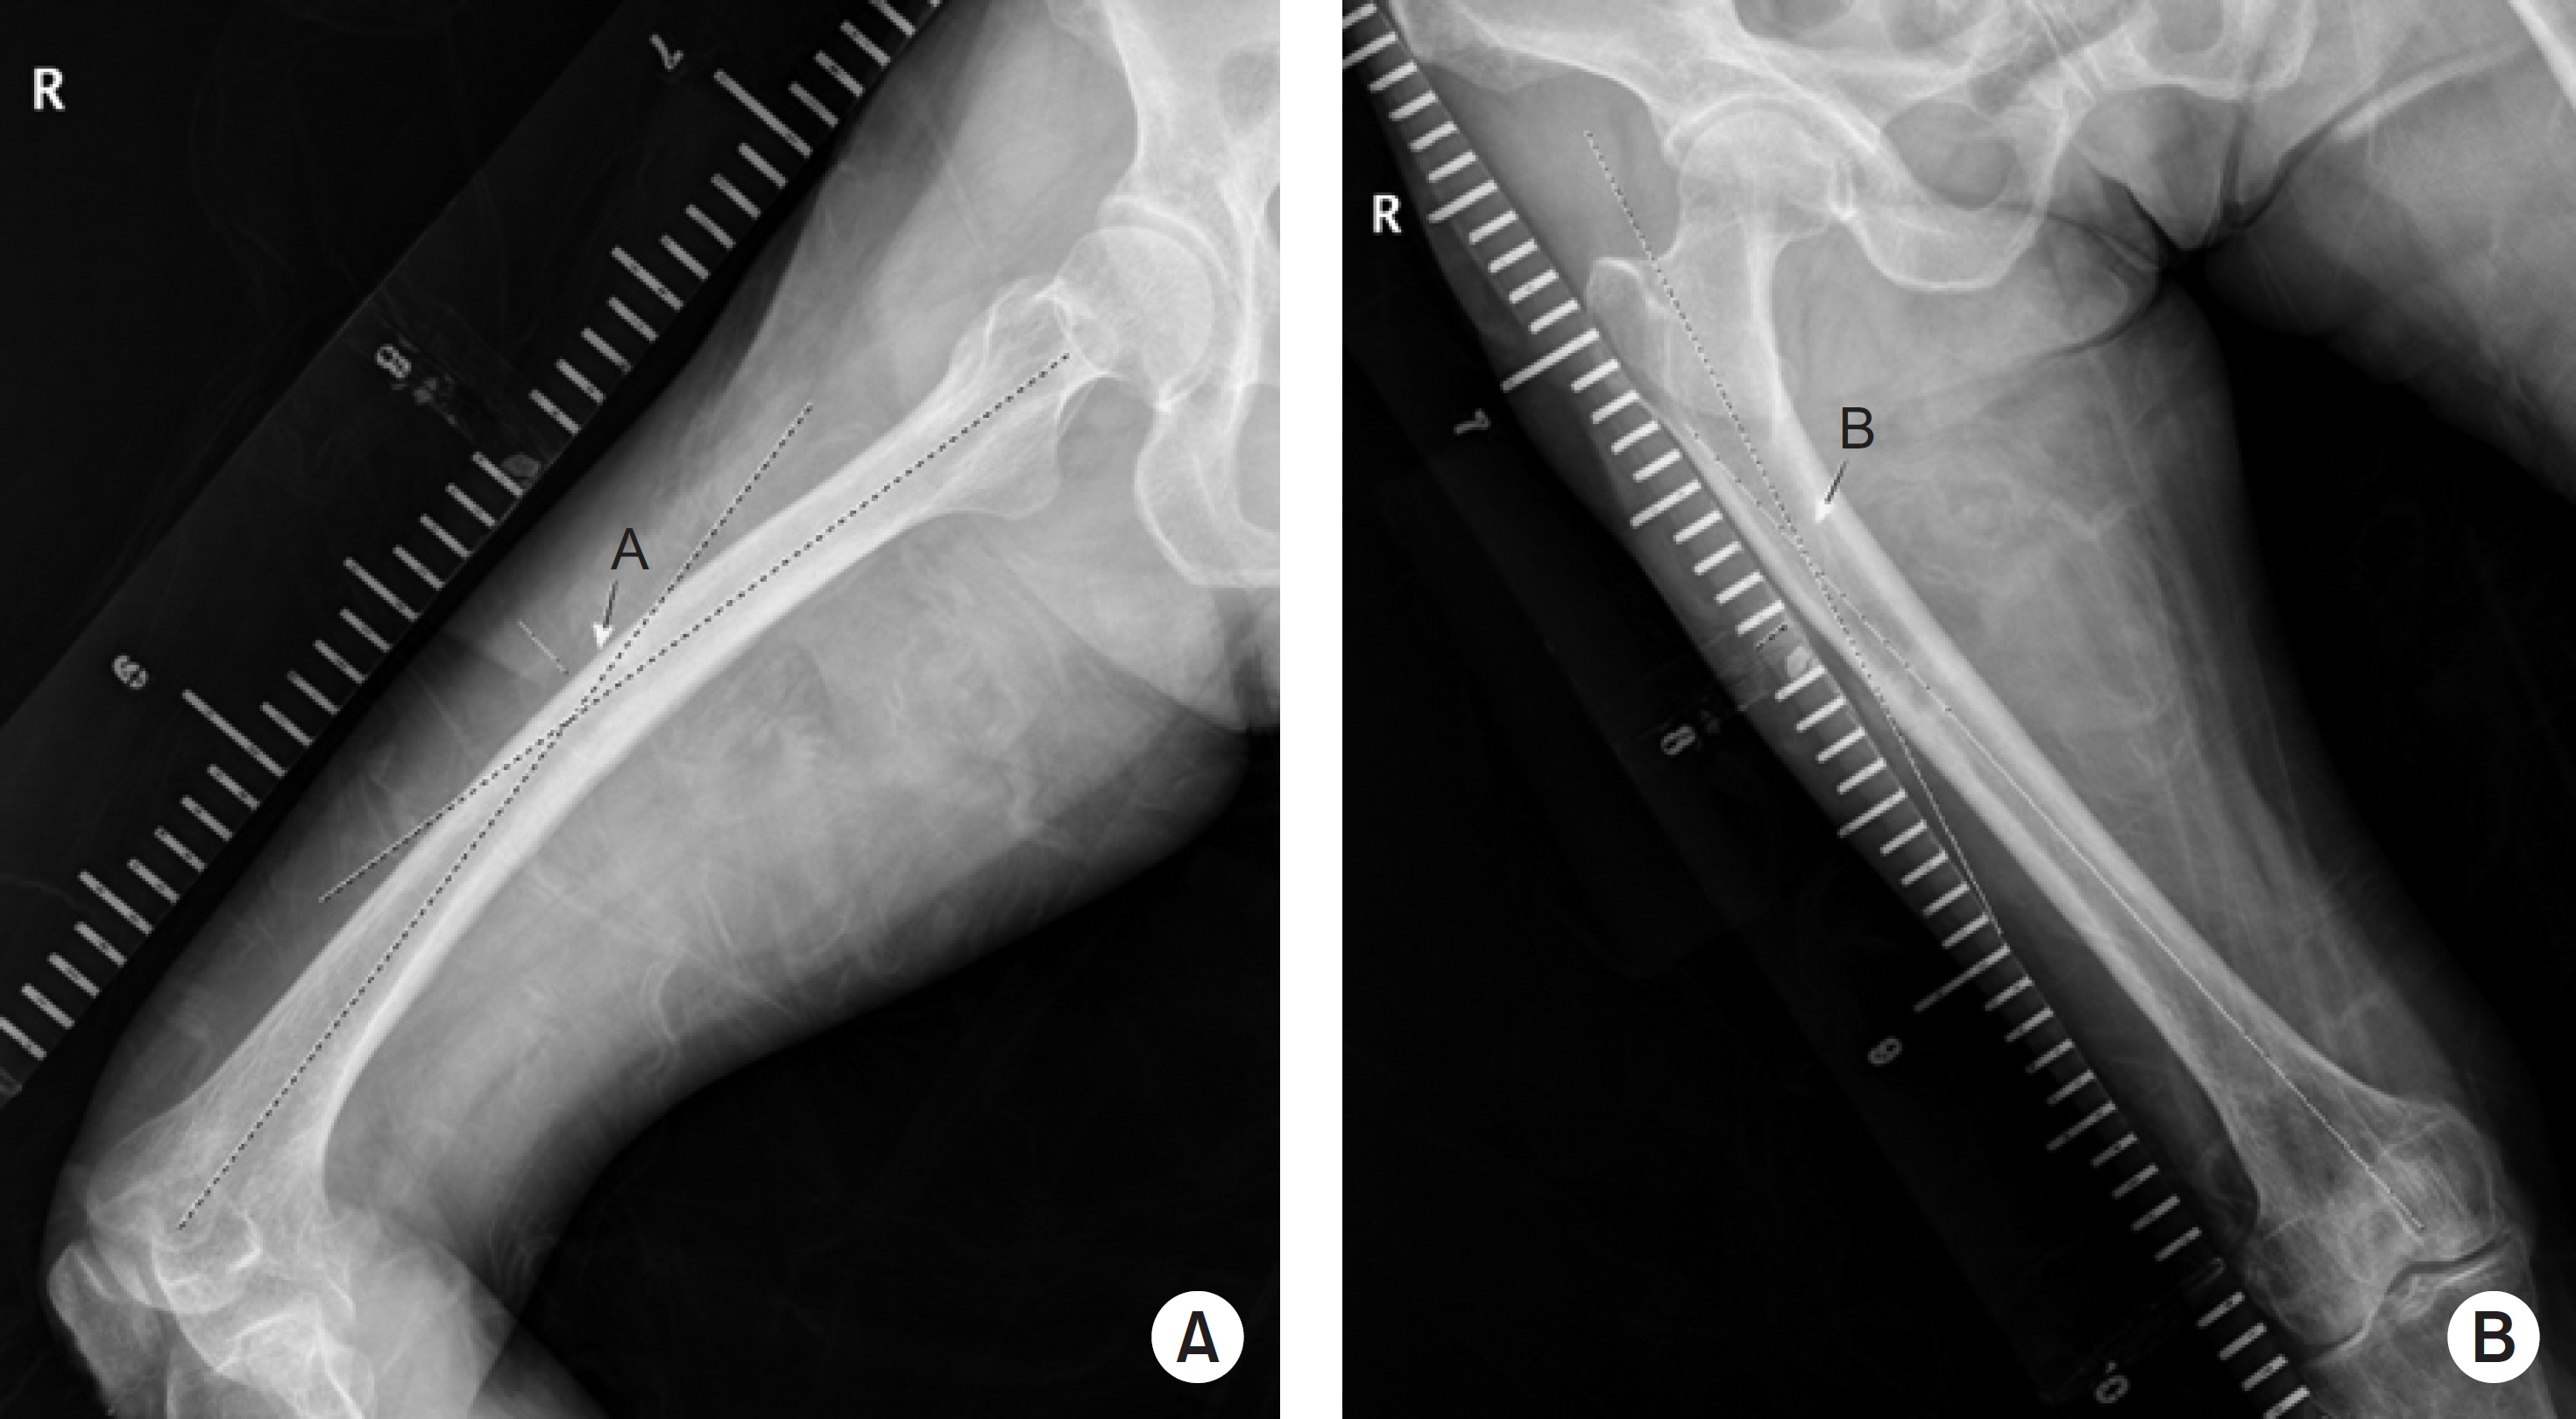

Fig. 1.

(A) Coronal view of the angle formed by two straight lines that pass the center of the proximal and distal parts, parallel to each other (letter ‘A’). (B) Lateral view of the same two lines (letter ‘B’).